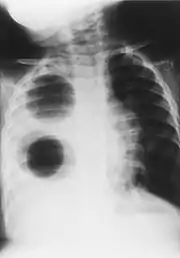

| Chest radiograph of a woman with unilateral pulmonary agenesis | |

- Chest X-ray is effective in detecting the traits of lung herniation.[1] The unaffected side of lung tends to undergo hypertrophy, and move towards the empty space in the chest wall on the opposite side.[1] This herniation could be indicated by fluoroscopy.[1] With age increasing, the herniation progresses and ease its detection.[1]